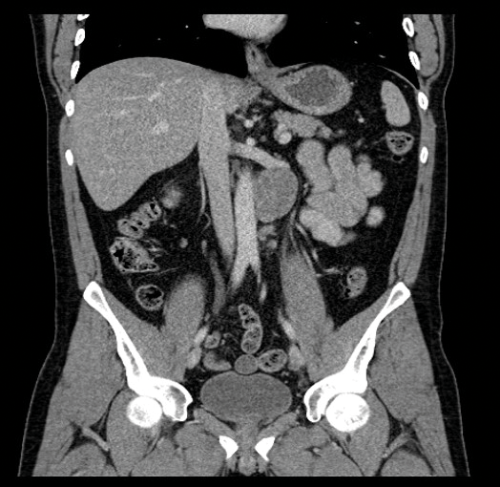

Stage two disease has abdominal lymph nodes; 2a nodes <2cm, 2b nodes 2-5cm, 2c at least one node >5cm. Retroperitoneal lymph nodes are the commonest site for metastatic disease and left sided tumours tend to spread to left para-aortic lymph nodes (Figure 3) and right sided tumours to aorto-caval or precaval nodes [3] (Figure 4). It is important to carefully evaluate the relevant area depending on the site of the tumour.

Figure 6. Coronal CT showing left para-aortic lymph node in the same patient as Figure 3.

Nodes may be massive and encase renal vessels, displacing the aorta or inferior vena cava (IVC) and this is important when reporting the staging CT (Figure 5). Coronal views can be very useful to demonstrate the overall length of nodal disease as sometimes, on axial imaging the size of the nodes can be underestimated (Figure 6). Teratoma nodes may contain some areas of calcification or low attenuation areas of necrosis, which are less often seen in seminoma lymph nodes. Retroperitoneal lymph nodes often respond very well to chemotherapy agents, but teratoma nodes may require retroperitoneal lymph node dissection if they do not respond or there remains a sizable node at the end of the treatment.